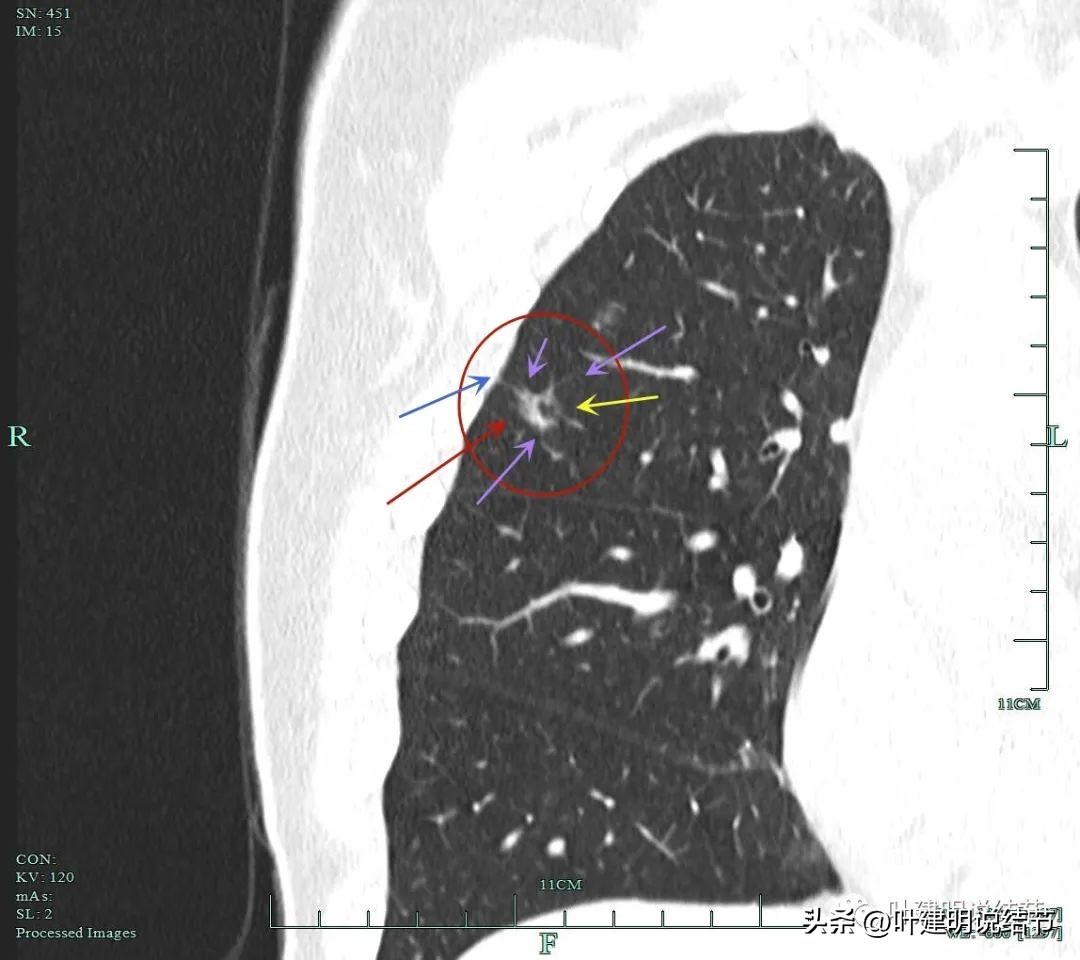

砖色箭头示病灶有分叶征;蓝色箭头示胸膜牵拉;紫色箭头示毛刺征;红色箭头示整体轮廓与瘤肺边界清。总体上看病灶有收缩力、有分叶与毛刺,而且灶内密度不均。是较为典型的浸润性腺癌影像表现。